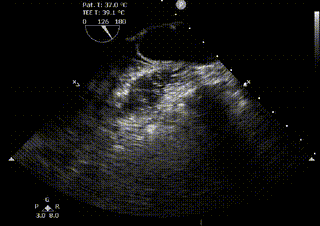

Upon arrival, an automated chest compression device was in place with ongoing cardiopulmonary resuscitation (CPR), end-tidal CO2 20mmHg, and had just received epinephrine. Patient moved to the gurney and is pulseless; CPR resumed. Supraglottic airway is immediately removed for a definitive endotracheal tube, while compressions were ongoing. Transesophageal echocardiography (TEE) transducer inserted after appropriate considerations were taken, and this is seen.

Figure 1. Shows ongoing chest compressions in the midesophageal long axis view (MeLAX). With the compressions it is noted the area of maximal compression (AMC) is over the left ventricular outflow tract (LVOT) and aortic valve (AV).